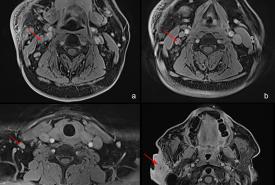

Recurrent Kimura Disease of the Submandibular Region After Prolonged Remission to Radiotherapy and Its Challenges

Case Report 29 Jan, 2026